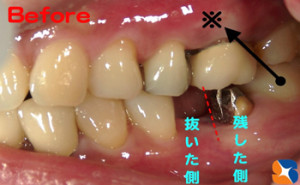

歯を守る 残す

コラム「歯を守る 残す」の画像